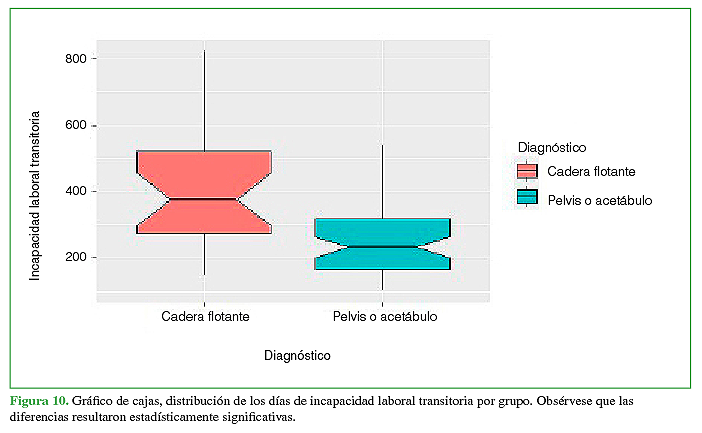

Resumen: Objetivo: Describir los tiempos de internación, cirugía y rehabilitación de una serie de pacientes con cadera flotante. El objetivo secundario fue comparar los resultados obtenidos en función de la reinserción laboral con los de pacientes que sufrieron fracturas de pelvis o acetábulo sin fractura femoral asociada. Materiales y Métodos: Estudio descriptivo, retrospectivo y multicéntrico de pacientes con trauma de pelvis y acetábulo de alta energía, divididos en dos grupos de estudio según la presencia de fractura de fémur asociada homolateral (cadera flotante) para su comparación, durante el período comprendido entre enero de 2014 y marzo de 2019. Resultados: Se incluyó a 102 pacientes con trauma de pelvis o acetábulo agrupados en 2 poblaciones según la presencia de cadera flotante (cadera flotante 23; pelvis/acetábulo 79). Las medianas de días de internación [cadera flotante 15,5 (rango 4-193); pelvis/acetábulo 7 (rango 3-31); p = 0,0001] y de la cantidad de cirugías por paciente [cadera flotante 5 (rango 3-8); pelvis/acetábulo 2 (rango 1-4); p = 0,0001] fueron mayores en los pacientes con cadera flotante. Además, la incapacidad laboral temporaria fue más alta (p = 0,00012), sin diferencias significativas en la tasa de recalificación laboral (p = 0,11). Conclusión: La asociación de la lesión cadera flotante aumentó significativamente el tiempo de internación, los procedimientos quirúrgicos necesarios y el tiempo de recuperación según la incapacidad laboral temporaria en pacientes con trauma de pelvis o acetábulo.

Abstract: Objective: We aim to describe the lengths of hospitalization, surgery, and rehabilitation of a series of patients with floating hip. As a secondary objective, to compare the outcomes obtained in terms of return to work in patients who had suffered fractures of the pelvis or acetabulum without an associated femoral fracture. Materials and Methods: Descriptive, retrospective, and multicenter study of patients with high-energy trauma to the pelvis and acetabulum divided into two study populations according to the presence of associated ipsilateral femur fracture (floating hip) for comparison, during the period January 2014 - March 2019. Results: 102 patients with pelvis and/or acetabulum trauma were included, grouped into 2 populations according to the presence of a floating hip (Floating hip: 23 patients; Pelvis/acetabulum: 79 patients). The median days of hospitalization [floating hip: median = 15.5 (range = 4-193); pelvis/acetabulum: 7 (3-31); p = 0.0001] and the number of surgeries per patient [FH: median = 5 (range = 3-8); pelvis/acetabulum: 2 (1-4); p = 0.0001] were higher in patients with floating hip. Additionally, temporary work disability was higher (p = 0.00012), with no significant differences in the rate of job retraining (p = 0.11). Conclusion: Floating hip significantly increased the length of hospitalization, necessary surgical procedures, and recovery times according to temporary work disability in patients with trauma to the pelvis and/or acetabulum.

Las diferencias entre los grupos con respecto a la incapacidad laboral temporaria resultaron estadísticamente significativas (p = 0,00012). No hubo diferencias estadísticamente significativas en la tasa de recalificación laboral, entre los grupos en función del diagnóstico de CF (p = 0,11) (Figuras 10y 11).

Al evaluar la cantidad de procedimientos realizados en ambos grupos, se halló una diferencia estadísticamente significativa, que fue mayor en los pacientes con CF. Creemos que tiene relación con la asociación de otras lesiones de partes blandas y no ortopédicas que pudieron demorar la estabilización esquelética. Asimismo, esta población requirió más días de internación. Con respecto a la incapacidad laboral temporaria quedó demostrada estadísticamente la gravedad que la CF trae aparejada en cuanto al tiempo que demoraron los pacientes con trauma de pelvis y acetábulo en lograr la reinserción laboral.

En nuestra serie, los pacientes con CF requirieron más procedimientos quirúrgicos y días de internación, y la incapacidad laboral transitoria fue mayor, con el consecuente aumento de los días de rehabilitación, frente a las fracturas aisladas de pelvis o acetábulo; no se hallaron diferencias en la tasa de recalificación laboral.